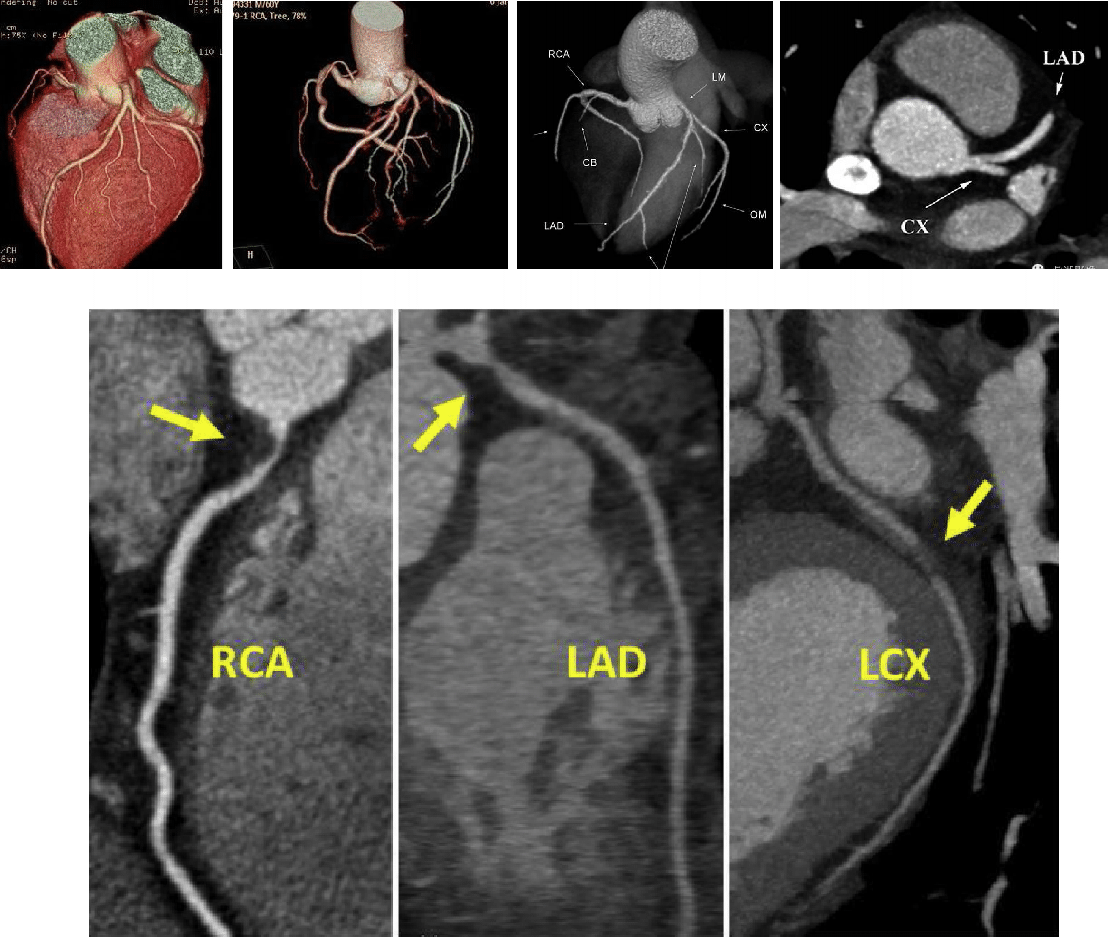

●冠脉CTA